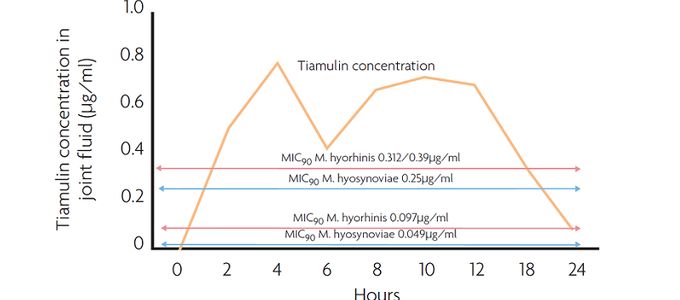

All remaining sows and boars are treated either in feed or in drinking water with a selected antimicrobial. This antimicrobial has not only to show a superb efficacy against M. hyopneumoniae in the laboratory but also to penetrate the targeted lung tissue to a large extent. Therefore, most successful eradication programmes have been conducted with tiamulin, which is a non-critical antimicrobial belonging to the class of pleuromutilines.

The minimal inhibitory concentration of tiamulin to inhibit growth of 90% (MIC90) of the M. hyopneumoniae strains tested is not more than 0.06μg/ml (Table 1).

This molecule does not only show an excellent absorption after oral administration and a low plasma protein binding capacity but also high tissue concentrations in the lung. The exposure to tiamulin is 18 times higher in lung tissue compared to plasma (Figure 2).

As the survival time of the pathogen outside the pig's body is reported to be short, a treatment duration of 14 consecutive days is advised. The daily dosage is 10mg tiamulin hydrogen fumarate per kg bodyweight. Special attention has to be paid to correct dosing, mainly for the sows in the lactation units. Sows refusing to eat are removed or injected with tiamulin for five consecutive days. If they still do not eat after injections, they should be removed from the herd.